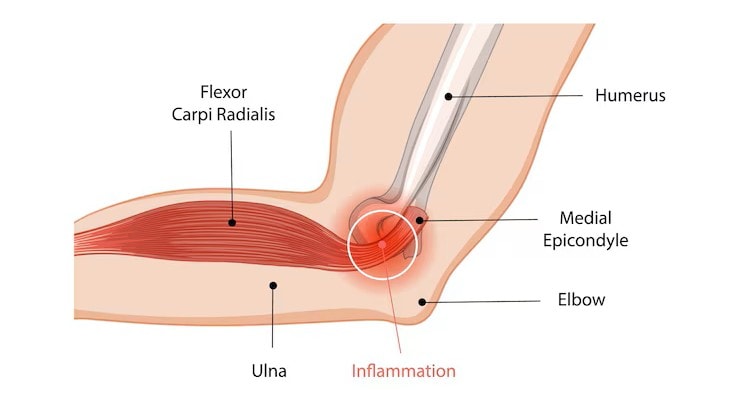

Origin

The flexor carpi radialis originates at the medial epicondyle of the humerus, a bony prominence on the inner elbow. From here, it runs down the forearm to the wrist, forming a crucial part of the common flexor tendon. This origin firmly anchors the muscle, enabling effective force exertion during wrist movements.

The medial epicondyle serves as a common origin for several forearm flexors, creating a coordinated system that facilitates various hand and wrist functions. This shared origin highlights the interconnectedness of forearm muscles in enabling complex movements.